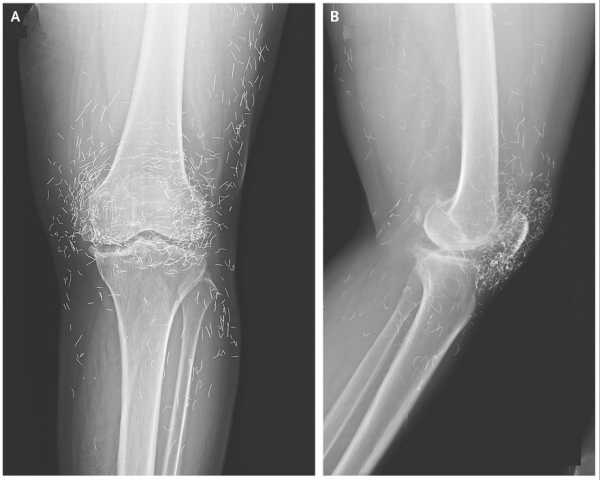

Рентгенівський знімок передньої (A) та бічної (B) частини лівого коліна пацієнта. Лінії – це крихітні золотисті нитки. (Зображення: The New England Journal of Medicine ©2013.)

Пізніше вона звернулася до лікарні, оскільки в неї дуже боліли коліна. Рентген лівого коліна показав, що великогомілкова кістка у внутрішній частині суглоба потовстила та затверділа. Також на внутрішніх частинах великогомілкової кістки та стегнової кістки біля колінного суглоба були кісткові нарости, які називаються шпорами.

Лікарі також побачили на рентгенівському знімку сотні цяток навколо колінного суглоба, які виявилися крихітними золотими нитками.

Діагноз: Лікарі дізналися, що нитки були введені жінці в рамках процедури акупунктури. Ці короткі стерильні золоті нитки були навмисно залишені в тканинах для забезпечення постійної стимуляції.

У своєму звіті про випадок захворювання коліна лікарі зазначили, що золоті нитки, введені під час акупунктури, можуть ускладнити читання рентгенівських знімків.

Інші попереджають, що ці вбудовані золоті нитки не дозволяють людям робити МРТ через ризик руху металу та пошкодження артерії.

Таким чином, лікарі зазначили, що медичні працівники повинні знати про потенційні фактори ризику, пов’язані з акупунктурою із золотими нитками. Однак той факт, що їх легко ідентифікувати на рентгенівських знімках, гарантує, що їхнє місцезнаходження можна буде відстежувати з часом, якщо це необхідно.